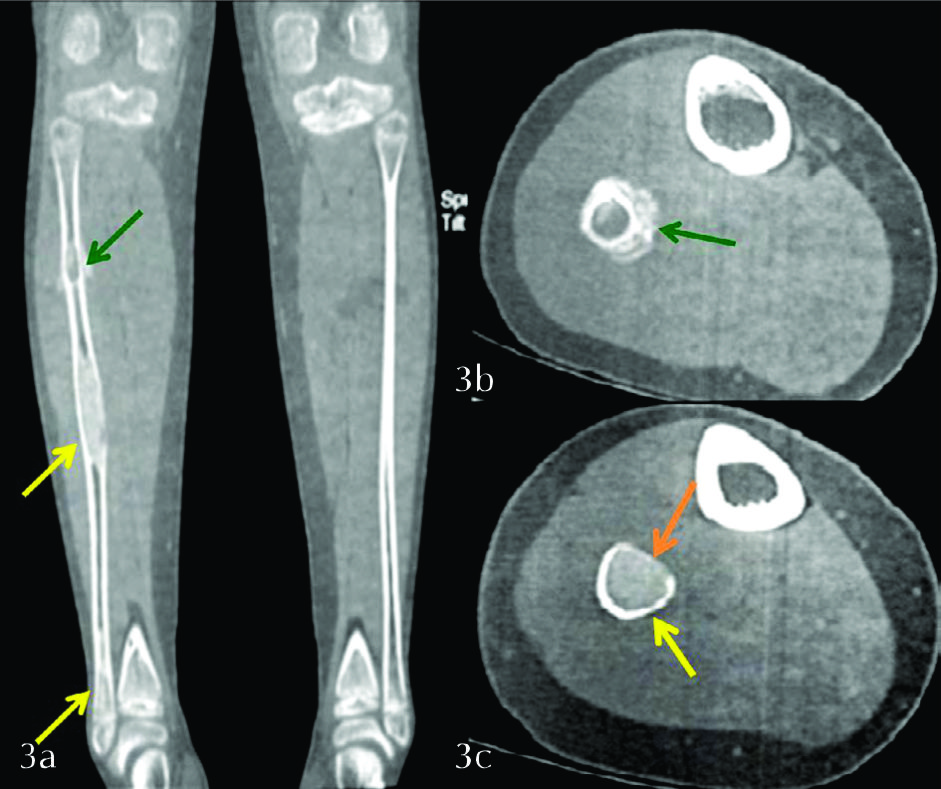

Se solicitó radiografía simple de pierna derecha en proyección frontal y de perfil (Ver fig. 1 y 2), que se completó con TC sin contraste a pedido del traumatólogo tratante (Ver fig. 3).

Ambos estudios constataron la presencia de tres lesiones líticas de baja agresividad, con características imagenológicas de DF. Solamente la lesión proximal presentó reacción perióstica de tipo ininterrumpido asociado a un trazo de fractura patológico.

Figura 3

TC de MMII con filtro duro. a) Corte seleccionado en el plano coronal, b) Corte seleccionado en el plano axial de la lesión superior, c) Corte seleccionado en el plano axial de la lesión del tercio medio. Se observa con mayor precisión la reacción perióstica de la lesión proximal (flechas verdes), la cual es ininterrumpida, de tipo sólido. El resto de las lesiones no presentan reacción perióstica de ningún tipo. Véase la matriz en “vidrio deslustrado” presente en las tres lesiones (flechas amarillas). Se identifica expansión y adelgazamiento de la cortical (flecha naranja).